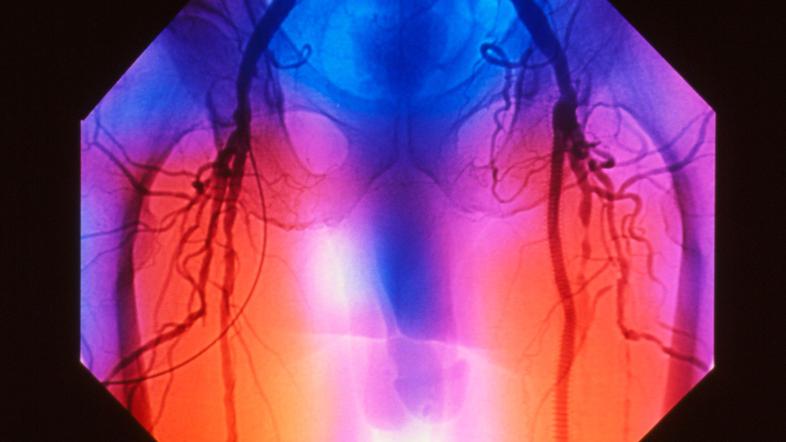

Periferna arterijska bolezen (PAB) je ena najpogostejših oblik napredovale ateroskleroze oziroma poapnenj žil in najpogosteje prizadene spodnje okončine.

Periferna arterijska bolezen | Avtor: Profimedia Profimedia

Bolezen povzroči, da so arterije spodnjih okončin slabše prehodne ali se celo povsem zaprejo. Takšne bolnike najbolj ogrožata srčni infarkt in možganska kap. Smrt zaradi srčno-žilnih bolezni je pri bolnikih s periferno arterijsko boleznijo dva do trikrat pogostejša kot pri ljudeh brez te bolezni.